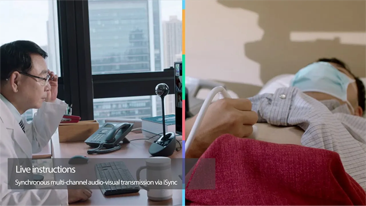

Desde que se fund├│ la compa?├Ła, Mindray ha explorado incansablemente nuevas formas de mejorar la confiabilidad del diagn├│stico. Con la revolucionaria tecnolog├Ła de ZONE Sonography?, la nueva plataforma ZST+ de Resona?7 lleva la calidad de la imagen por ecograf├Ła a un nivel superior mediante el procesamiento de datos de canal y la adquisici├│n de zona.

Adem├Īs de la calidad de imagen de primer nivel, Resona?7 tambi├®n mejora las capacidades de investigaci├│n cl├Łnica con el revolucionario V?Flow para la evaluaci├│n hemodin├Īmica vascular y con la adquisici├│n de planos m├Īs inteligente a partir de conjuntos de datos 3D para el diagn├│stico del SNC fetal. Al combinar el funcionamiento multit├Īctil basado en gestos m├Īs intuitivo y todas las caracter├Łsticas cl├Łnicas esenciales, Resona?7 realmente lidera las novedades en innovaci├│n de ecograf├Łas.